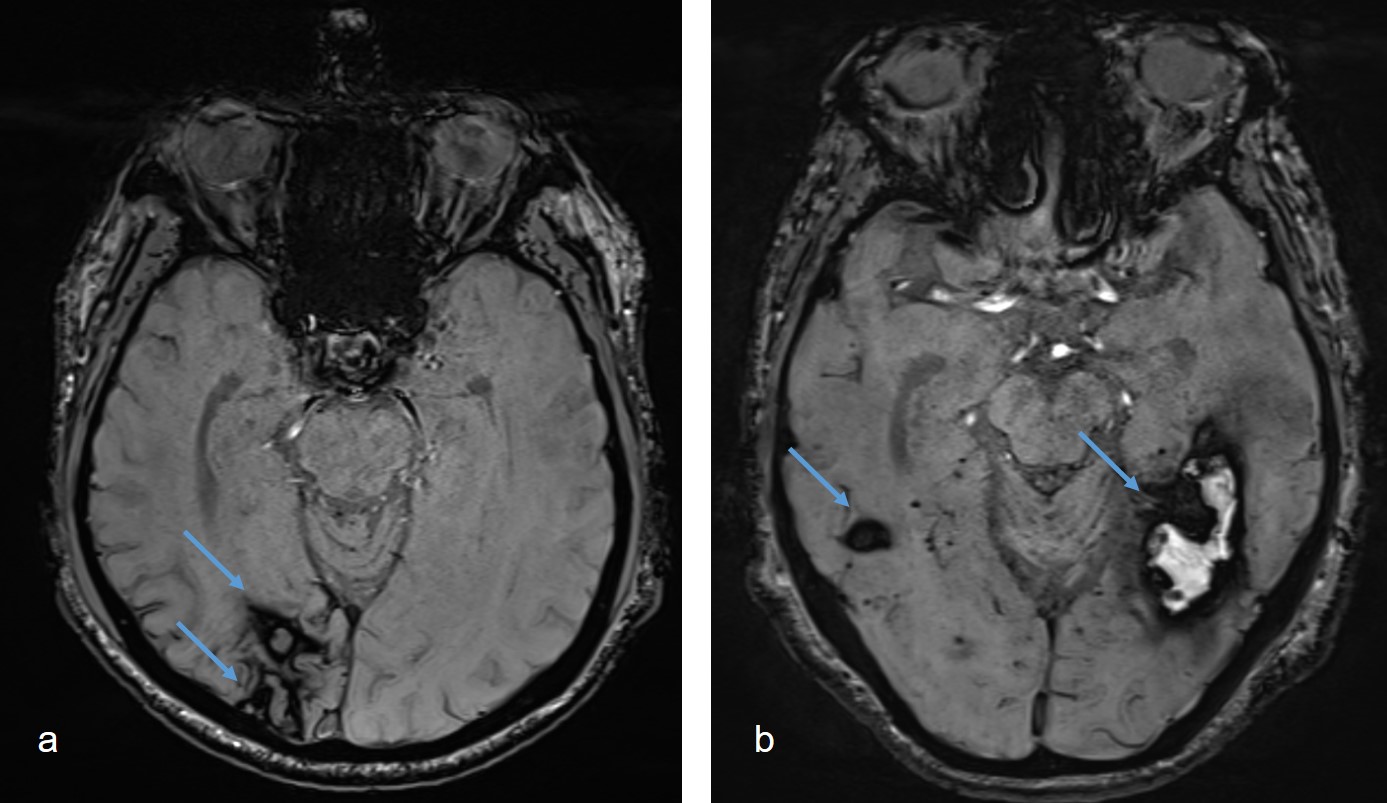

Eine europaweite Kollaboration im Rahmen von EURECA, unter der Leitung eines Forschungsteams der Universitätsklinik für Neurologie am Inselspital, untersuchte über 700 Patient:innen, die mehrere Hirnblutungen erlitten hatten. Die Studie zeigt, dass Rückfälle häufiger in der Nähe einer früheren Hirnblutung auftreten. Dies trifft insbesondere dann zu, wenn diese Hirnblutungen kurz aufeinander folgen. Die Ergebnisse deuten darauf hin, dass lokale Faktoren im Gewebe eine Rolle spielen und die Erforschung neuer Therapieansätze ermöglichen könnten. Die Studie wurde im JAMA Neurology Journal veröffentlicht.